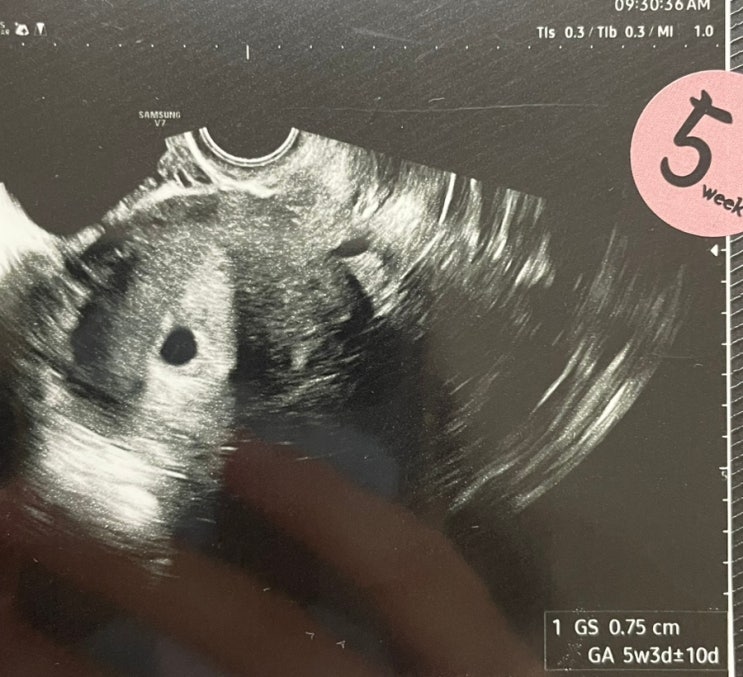

임신일기 | 고사난자 후 임신 | 바우처로 임신준비영양제 구입 | 임신 5주 0일 아기집 확인 5주 6일 난황 확인⭐️

임신일기 고사난자 후 임신 ( 고사난자는 초음파 상 임신 낭은 확인되지만 배아(태아)가 보이지 않는 경우)...